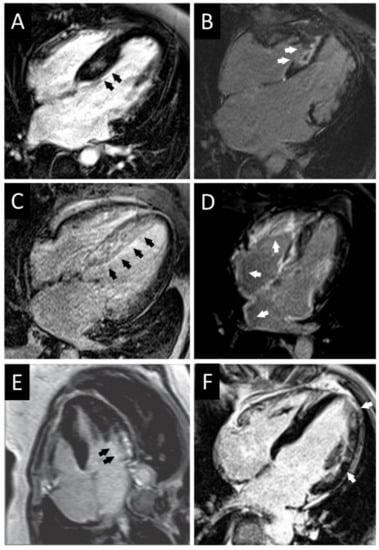

| CMR | LGE in most hypertrophied regionsHigh native T1 values | - | Diffuse subendocardial LGE (“zebra pattern”), difficulty in nulling the myocardial signal on phase sensitive inversion recovery sequences. High native T1 values | Mid-mural LGE on basal segment of non-hypertrophied inferolateral wall. Low native T1 values | LGE and high T1 values in the advanced stage of the disease |